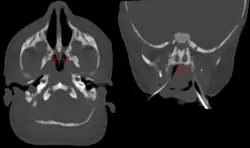

Bei Verdacht auf eine Choanalatresie kann mit einem weichen Katheter die Durchgängigkeit zum Rachenraum geprüft werden. Dem gleichen Zweck dient eine Lufteinblasung mit einem Ballon. Weitere diagnostische Schritte sind die Untersuchung mit dem Nasenspekulum und die Nasenendoskopie. Je nach Klärungsbedarf sind ein CT oder ein MRT einzusetzen. Choanalatresien treten zu 10 % bis 50 % mit anderen Missbildungen auf.